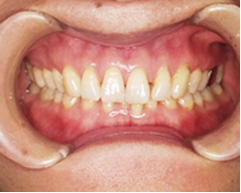

写真(1)

治療前

下の前歯が奥に入っていて前に上に飛び出してきて上の前歯に隙間ができています。

下の歯が上の歯に隠れてしまい、ほとんど見えません。顎を動かそうにも上の歯が邪魔で顎の関節に大きな負担がかかっています。